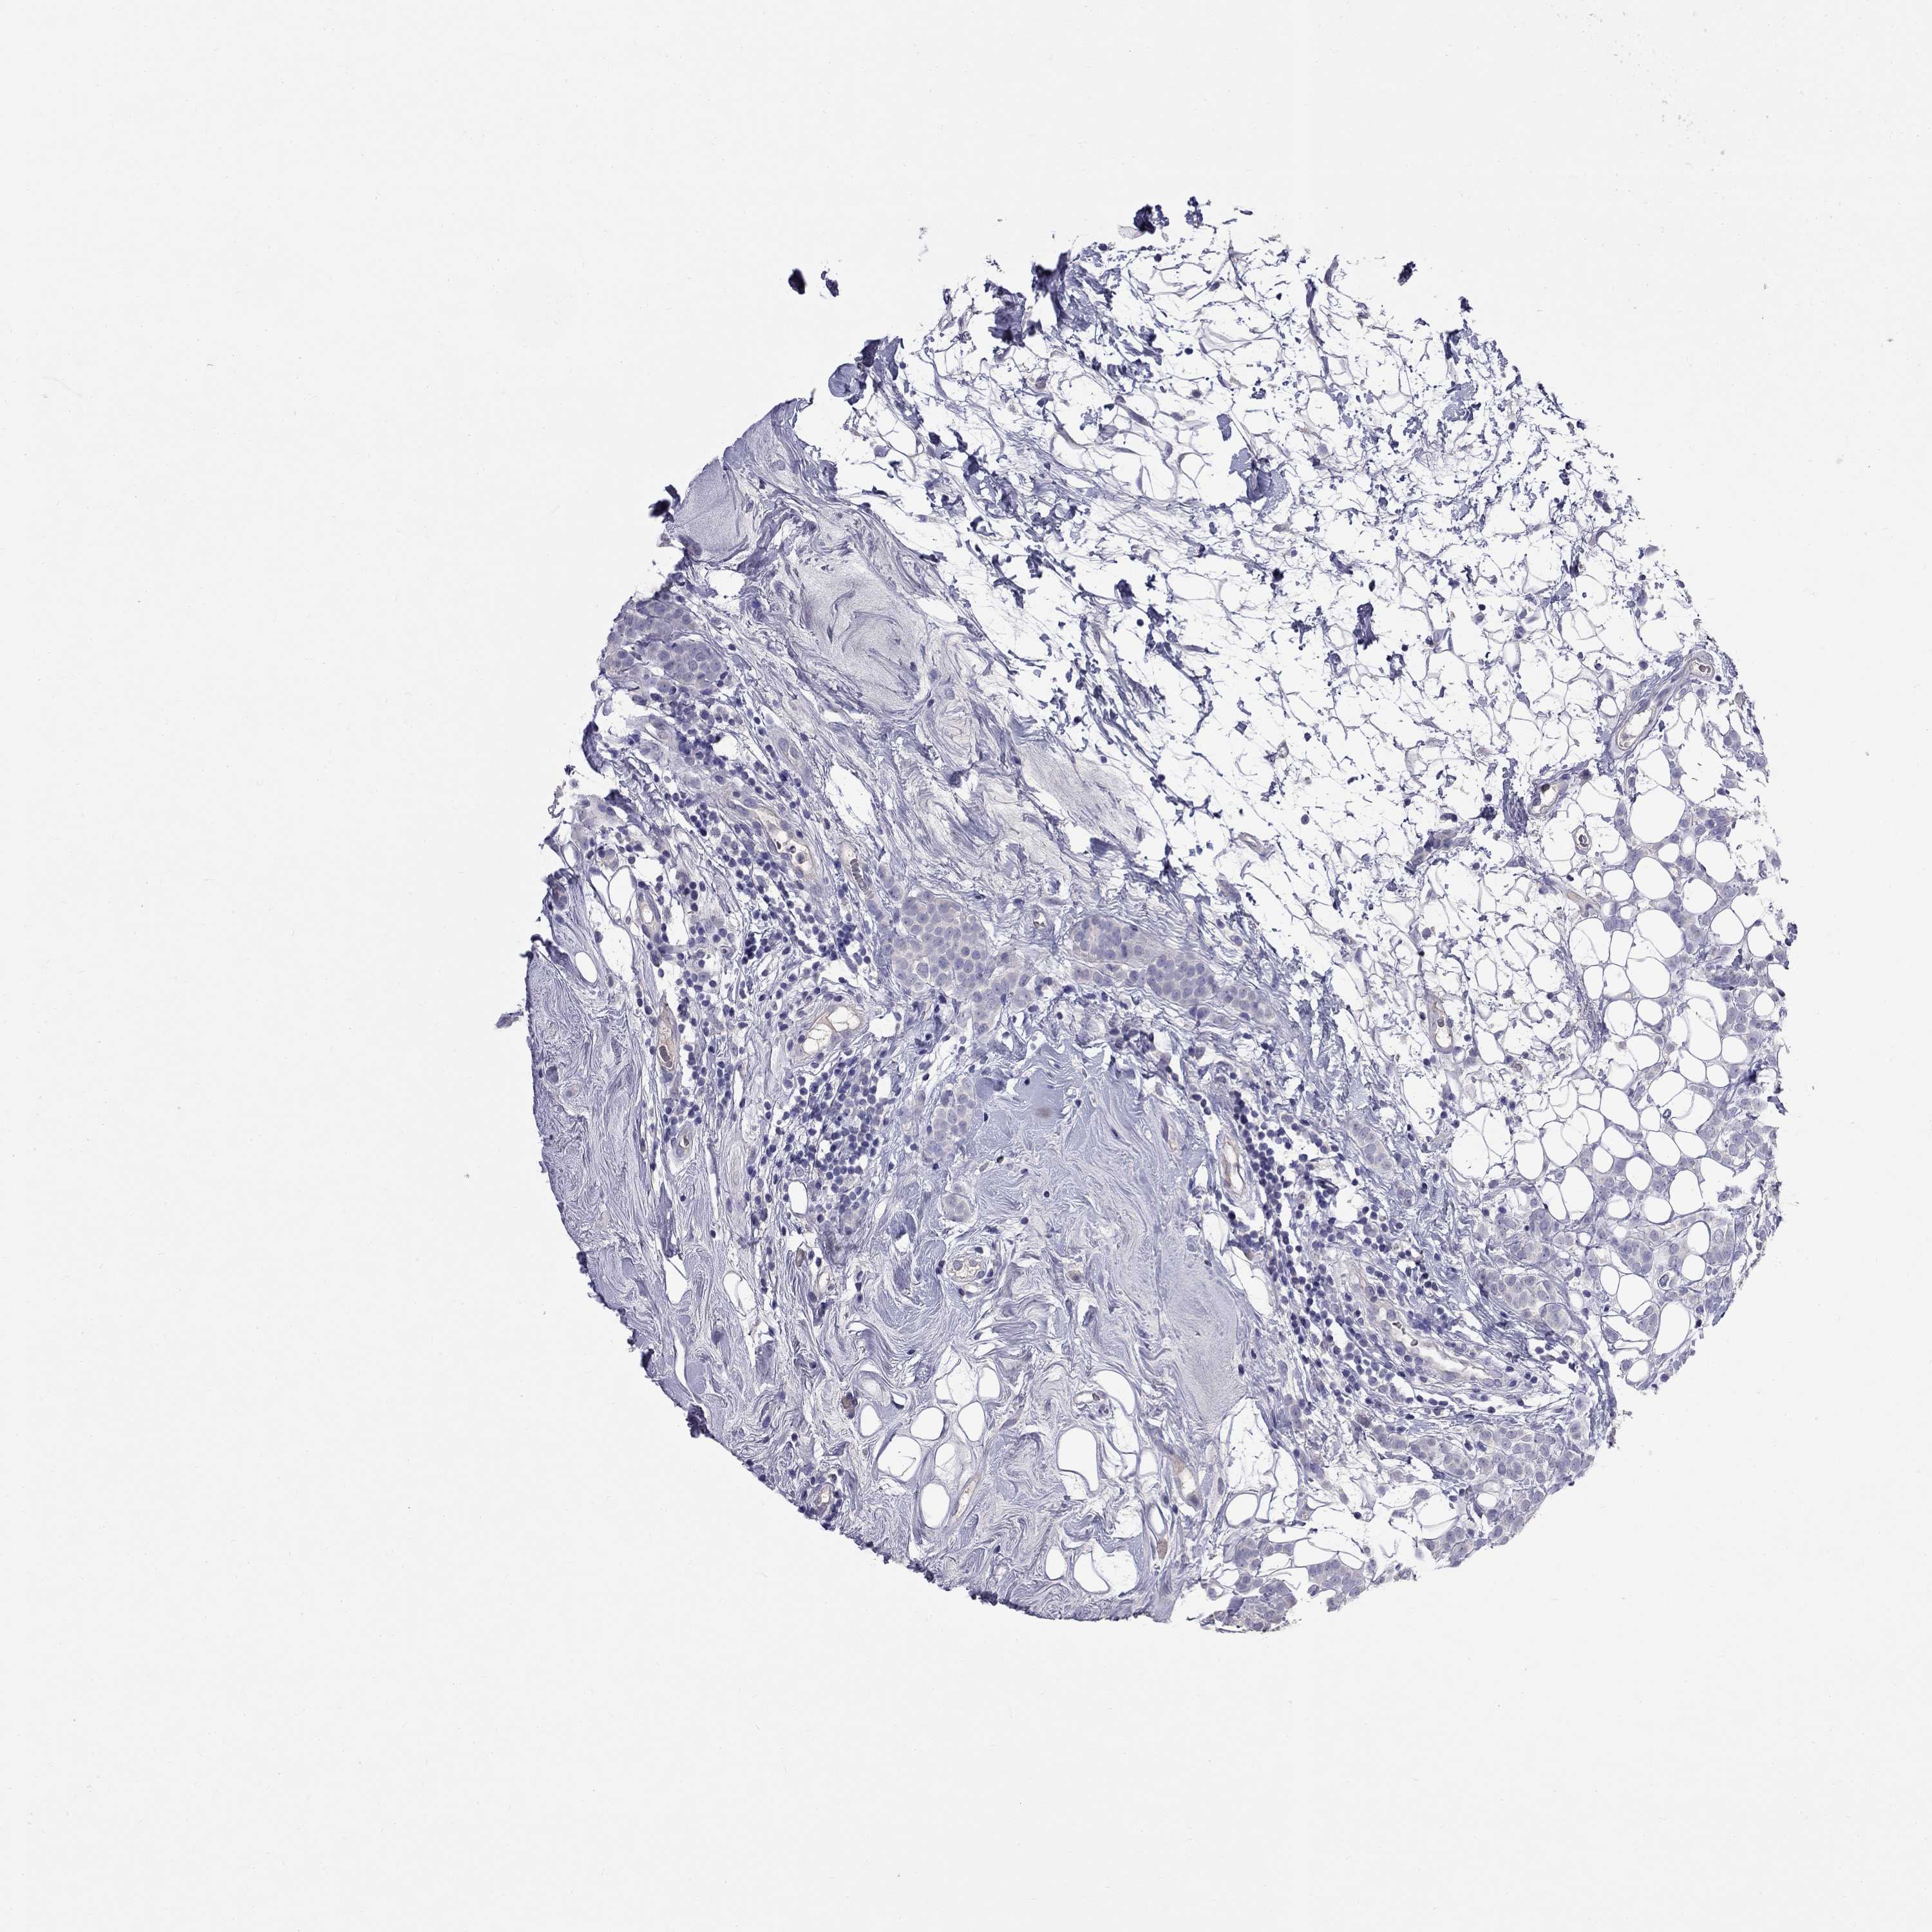

CANCER BREAST CANCER Show tissue menu

BRCA TCGA BRCA VALIDATION PROTEIN EXPRESSION